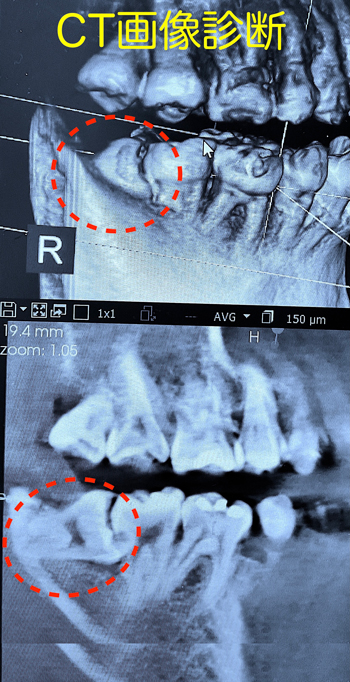

横向きの超難抜歯に、